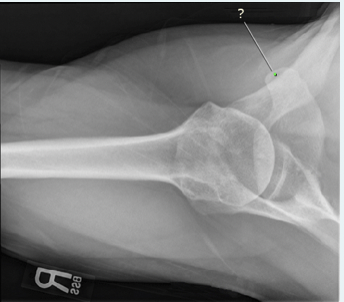

The white line is pointing to what anatomical part?

a.acromion process

b.clavicle

c.coracoid process

d.glenoid fossa

A